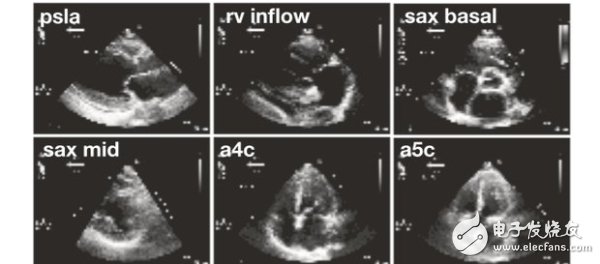

7037人工智能诊断心脏病比人类更快更准?

这个星球上的人们,或许还没有做好迎接人工智能医生的准备。不过,加州大学旧金山分校(UCSF) 的研究人员培育的AI,已经在心脏图像的分类比赛上,超过了参赛的人类心血管医师。